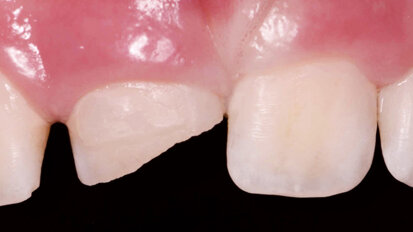

Hybridní terapie alignery